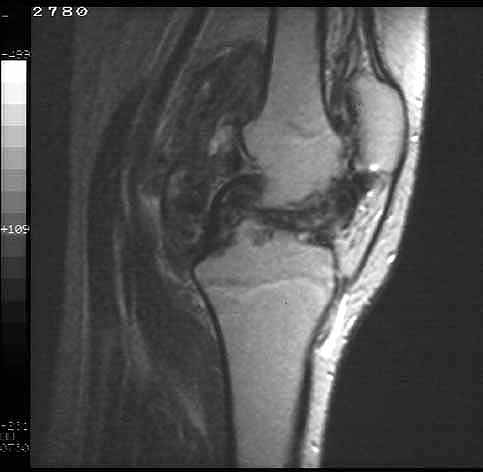

La Resonancia nuclear magnética aporta la información más característica en el diagnóstico diferencial entre alteraciones tumorales de partes blandas articulares (23), en la sinovitis villonodular pigmentada (24) . La RNM identifica hemosiderina, derrame articular e hiperplasia sinovial, sin destrucción significativa de la articulación. Además , permite detallar la extensión y distribución de la enfermedad en la articulación .(figuras 4 y 5 ).